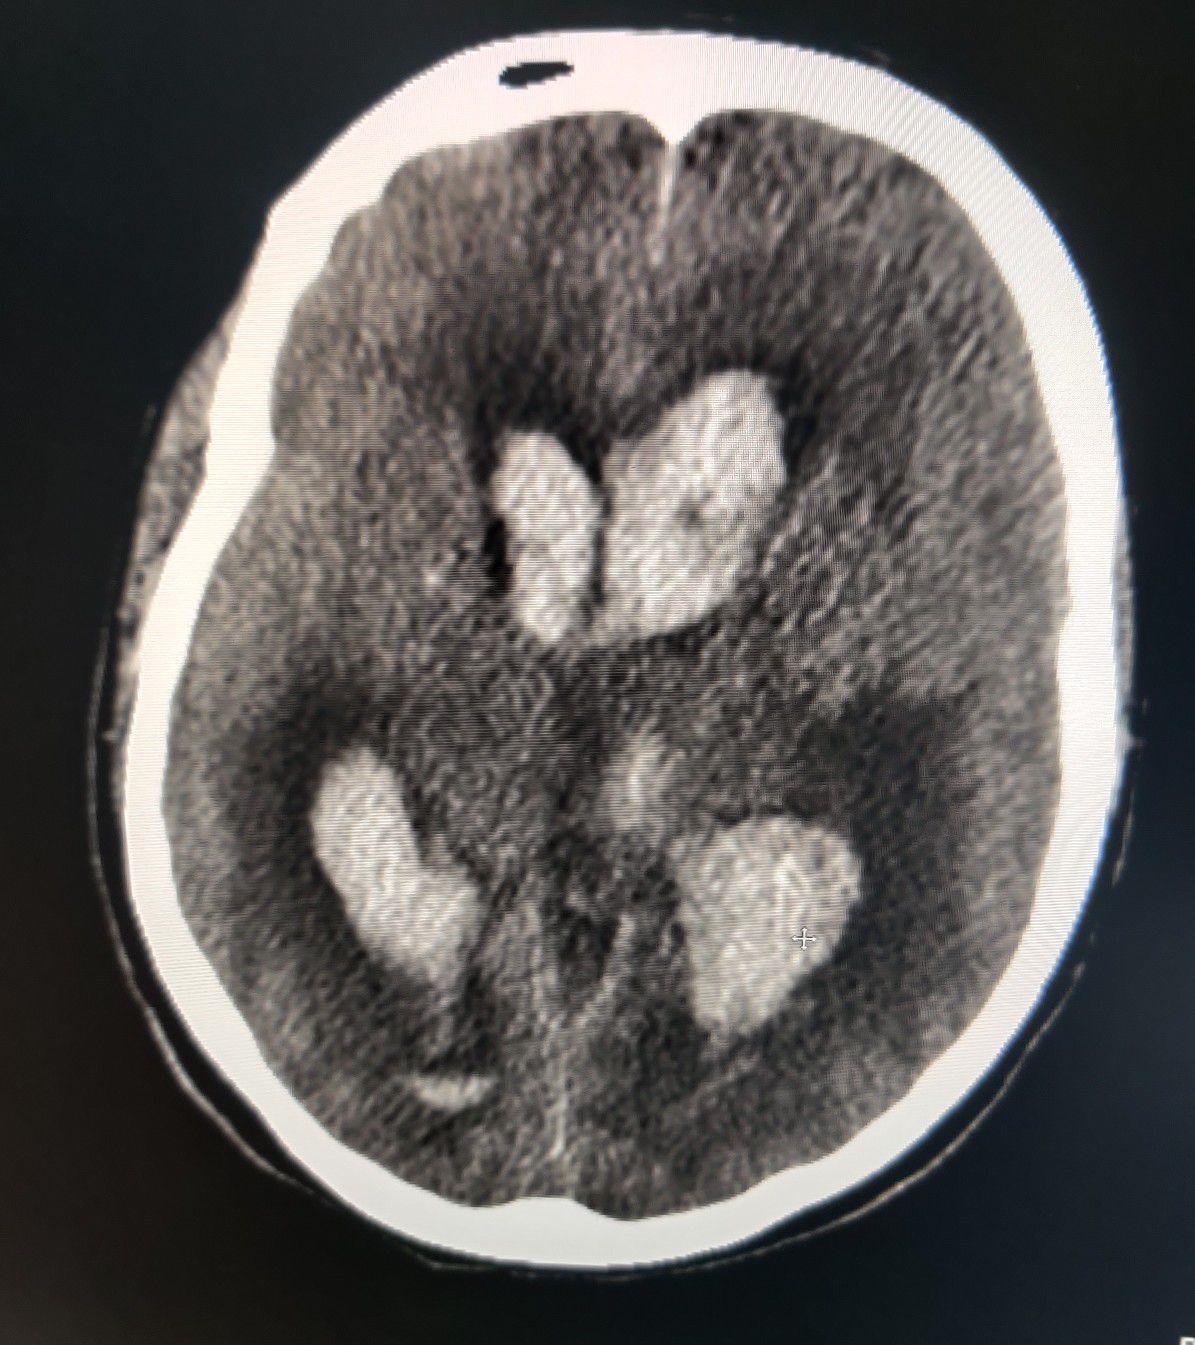

B/L Hemorrhagic CVA including lateral ventricles and 3rd Ventricle

Stroke

Hemorrhagic

Bleed